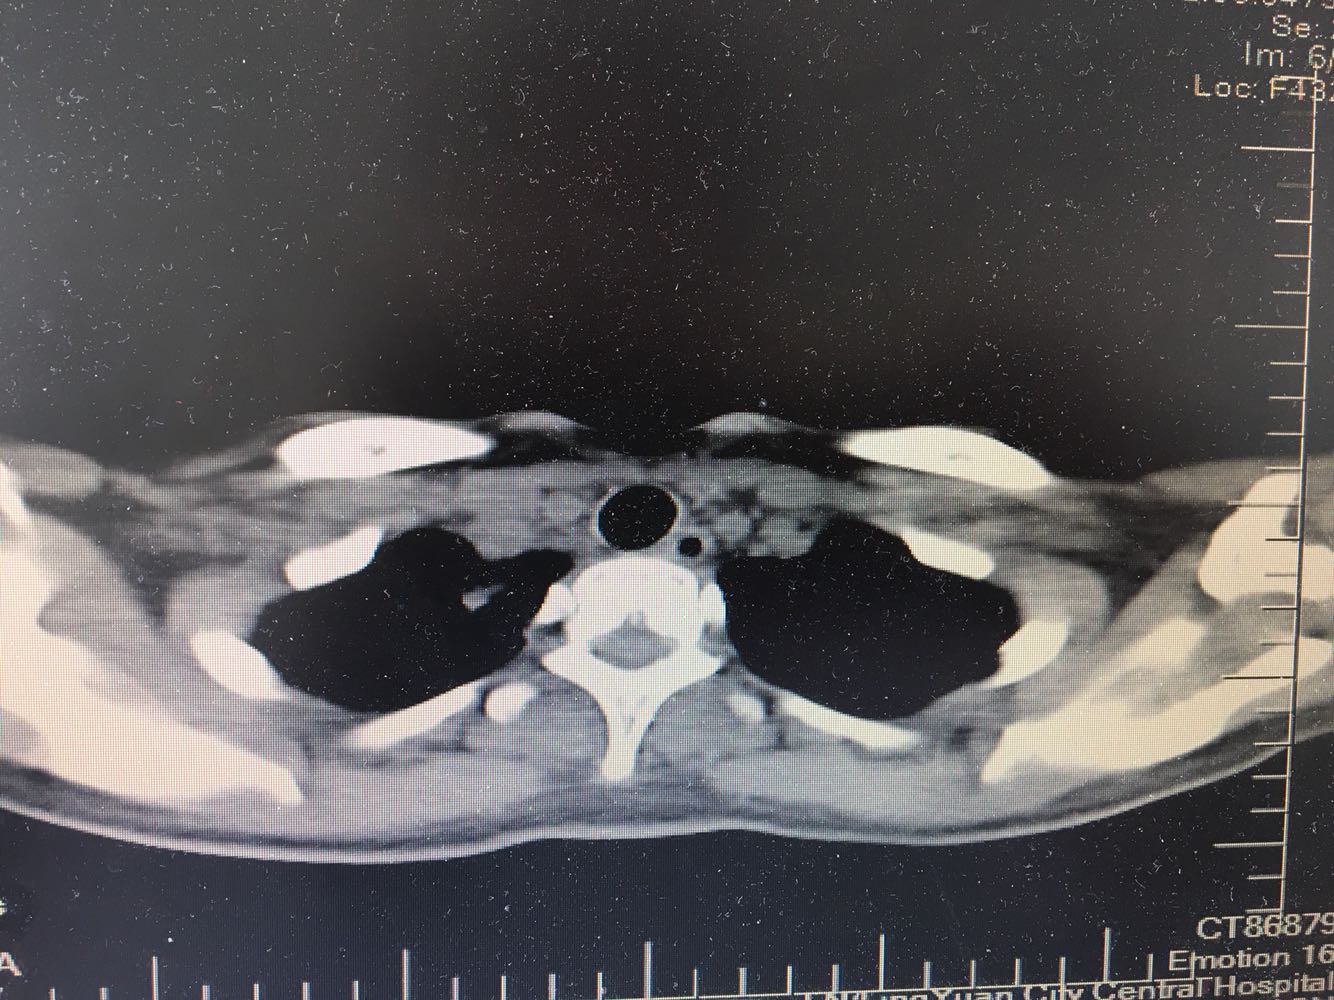

女,26岁,咳嗽1周,咳痰不畅,咽喉痒,口服阿莫西林无好转,昨日发热,体温38.5摄氏度,于门诊查肺CT后以肺炎收入院,病来无盗汗,无咳血,无消瘦及乏力,无头痛,无肢体酸痛,饮食睡眠可,二便正常

神清言明,咽部无充血,扁桃体不大,双肺呼吸音清,无罗音,服软无压痛。

支原体抗体1:160,结核抗体弱阳性。支原体肺炎个别可见上叶病变,该患无结核中毒症状,考虑支原体肺炎可能性大,但肺尖为结核好发部位,需要抗炎治疗后复查观察疗效。